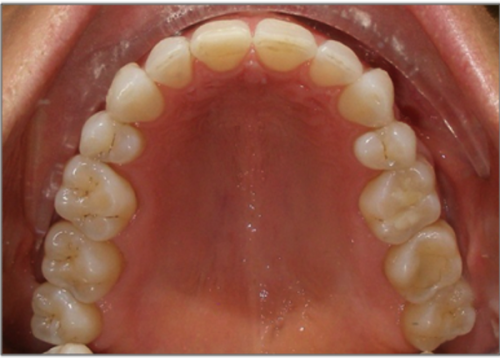

44 year old female:

Diagnosis:

- Upper and lower arch collapse due to missing teeth

- Retrusive angulation of upper & lower front teeth

- Severe collision and wear of front teeth

Treatment:

- Combination of Invisalign and braces

- Creating space for placement of an implant in the lower arch

- 28 months